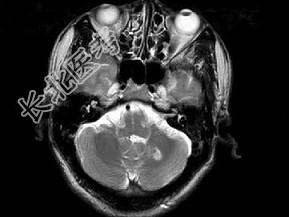

- 单项选择题男,49岁, 右侧肢体无力10余天,伴头昏行走不稳, 根据所提供图像,最可能的诊断是 ( )

E、颅内多发海绵状血管瘤